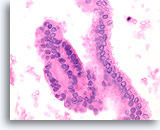

Afbeelding 14

Benigne, hyperplastisch/adenomatoïde nodule, schildklier FNA, celblok.

Let op het afgeplatte cytoplasma in e microfollikels vergeleken met het kubusvormige tot cilindrische cytoplasma van het macrofolliculaire epitheel linksboven. Let ook op het waterige colloïde in één follikel (pijl) vergeleken met het dicht opeengepakte colloïde in de microfollikels.

40X

Afbeelding 14

Benigne, hyperplastisch/adenomatoïde nodule, schildklier FNA, celblok.

Let op het afgeplatte cytoplasma in e microfollikels vergeleken met het kubusvormige tot cilindrische cytoplasma van het macrofolliculaire epitheel linksboven. Let ook op het waterige colloïde in één follikel (pijl) vergeleken met het dicht opeengepakte colloïde in de microfollikels.

40X